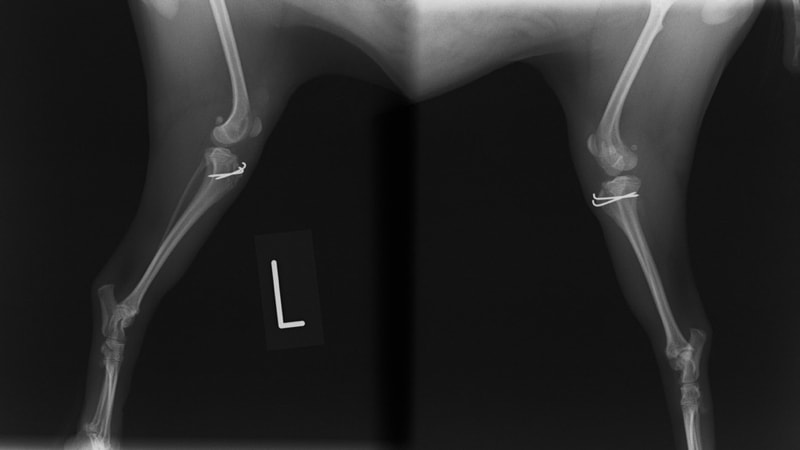

■ 症例22 ポメラニアン 1歳5か月 去勢雄

左後肢の挙上を主訴に来院した。整形学的検査、レントゲン検査より左右の膝蓋骨脱臼(左GradeⅡ〜Ⅲ、右Grade Ⅱ)を認めた。また、脛骨の前方引き出し試験の際に、引き出し兆候は認められないものの、疼痛が認められたため、前十字靭帯の損傷が疑われた。術中における、目視および関節内の操作によって、前十字靭帯の損傷や過伸展といった異常が認められなかったため、膝蓋骨脱臼の整復のみ実施した。手術手技は縫工筋及び内側広筋の解放、脛骨粗面の外側転位、滑車ブロック形造溝術、内外側関節包の縫縮を実施した。本症例は跛行もなく経過良好である。しかし、頸骨高平部の角度(TPA)が 右26.2°、左24.9°であり、解剖学的に前十字靭帯損傷のリスクが高いことから今後の経過に注意が必要である。